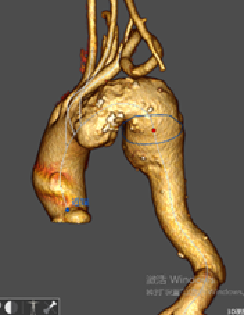

★ 病例5:解剖变异

(右位弓,迷走右锁骨下动脉)

释放方法和正常手术相同,但方向相反,需要调整。特别是分支的走向测试了该装置适应不同解剖结构的能力和便利性。

术后血管造影显示,所有分支方向与患者血管解剖结构匹配,尤其是无名动脉,外侧成近90°角,无内漏发生。随访显示所有分支通畅,无扭曲或迂曲,无卒中及内漏。